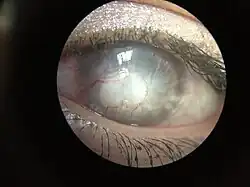

Corneal neovascularization (CNV) is the in-growth of new blood vessels from the pericorneal plexus into avascular corneal tissue as a result of oxygen deprivation.[1] Maintaining avascularity of the corneal stroma is an important aspect of healthy corneal physiology as it is required for corneal transparency and optimal vision. A decrease in corneal transparency causes visual acuity deterioration. Corneal tissue is avascular in nature and the presence of vascularization, which can be deep or superficial, is always pathologically related.[2]

Corneal neovascularization is a sight-threatening condition that can be caused by inflammation related to infection, chemical injury, autoimmune conditions, immune hypersensitivity, post-corneal transplantation, and traumatic conditions among other ocular pathologies. Common causes of CNV within the cornea include trachoma, corneal ulcers, phlyctenular keratoconjunctivitis, rosacea keratitis, interstitial keratitis, sclerosing keratitis, chemical burns, and wearing contact lenses for over-extended periods of time.[3] Superficial presentations of CNV are usually associated with contact lens wear, while deep presentations may be caused by chronic inflammatory and anterior segment ocular diseases.[4]